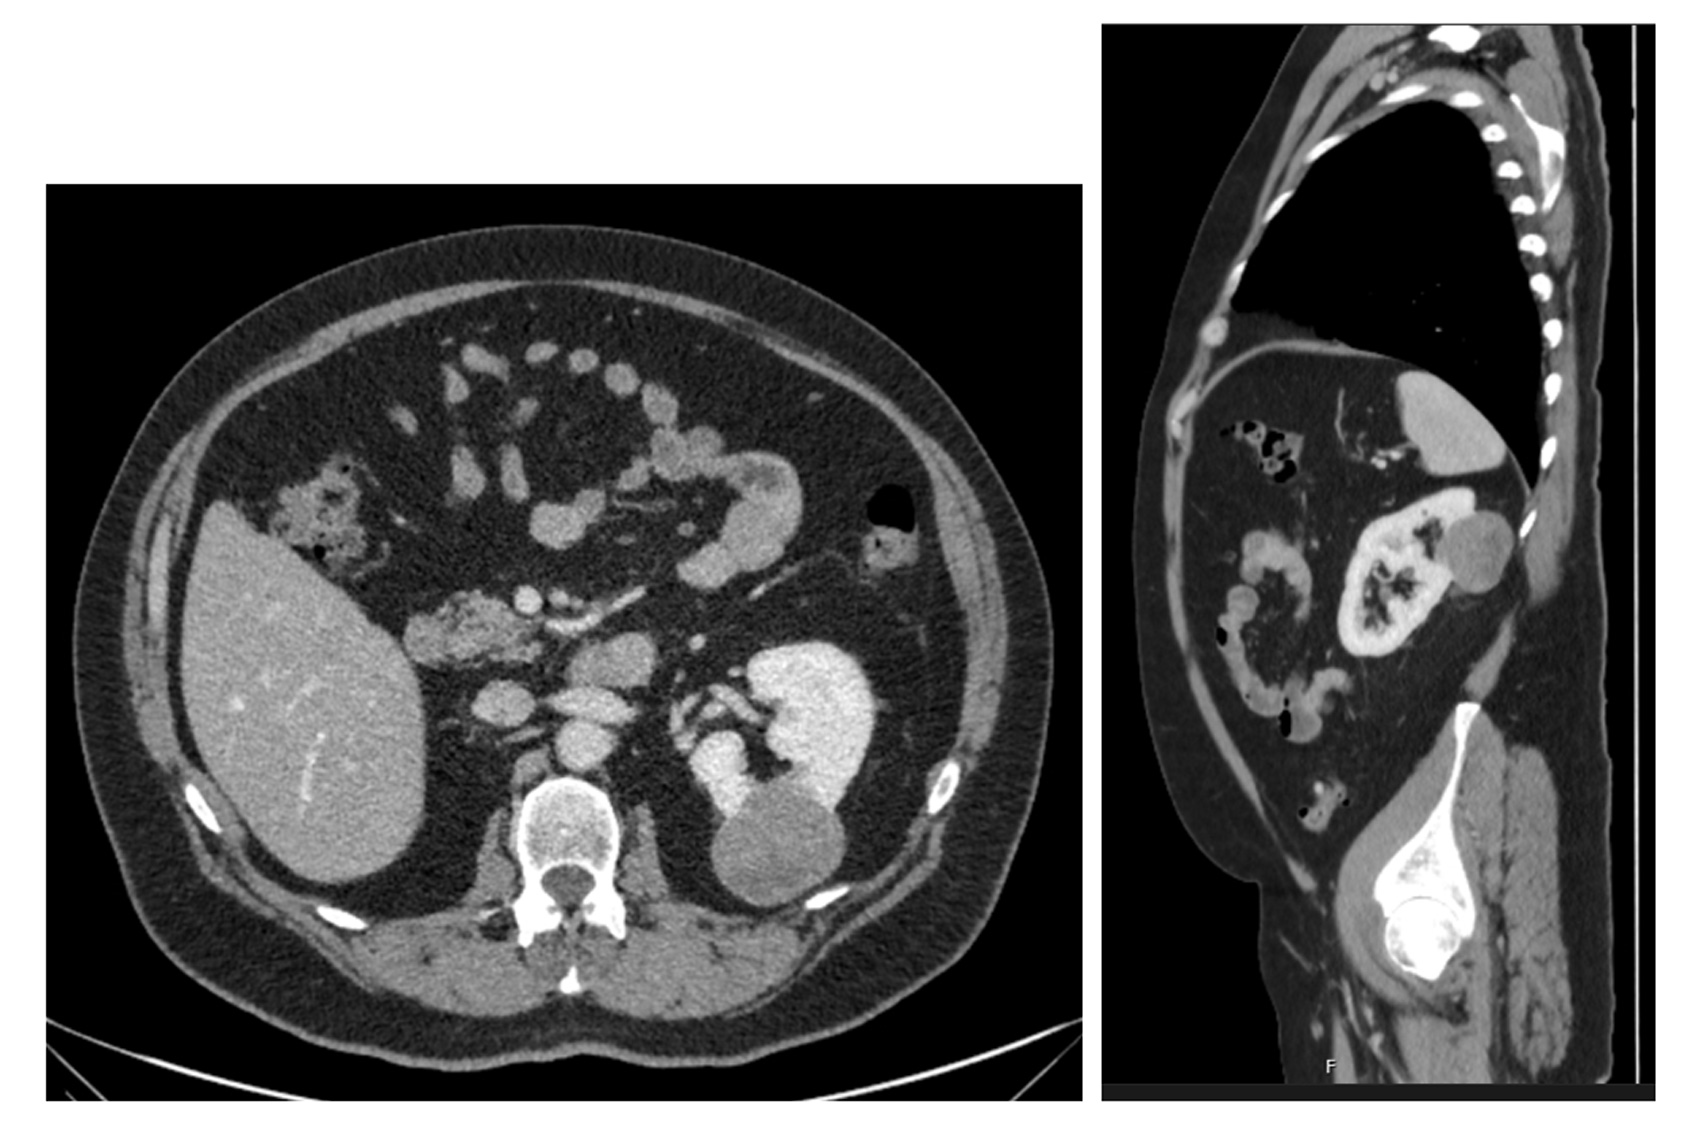

Figure 1: CT (axial and sagittal) views of the renal mass.

A 69-year-old male with a single left kidney underwent an open left partial nephrectomy for an incidentally diagnosed 5cm left renal mass with possible early collecting system invasion (stage T1b N0 M0) (Figure 1). Prior biopsy showed a papillary renal cell carcinoma type 1. This was found during investigations for episodes of macroscopic haematuria. He was known to have an atrophied right kidney since childhood. He was an ex-smoker (75 pack-year history) and other comorbidities included elevated body mass index (BMI) of 32.5, hypertension, and alcohol excess.